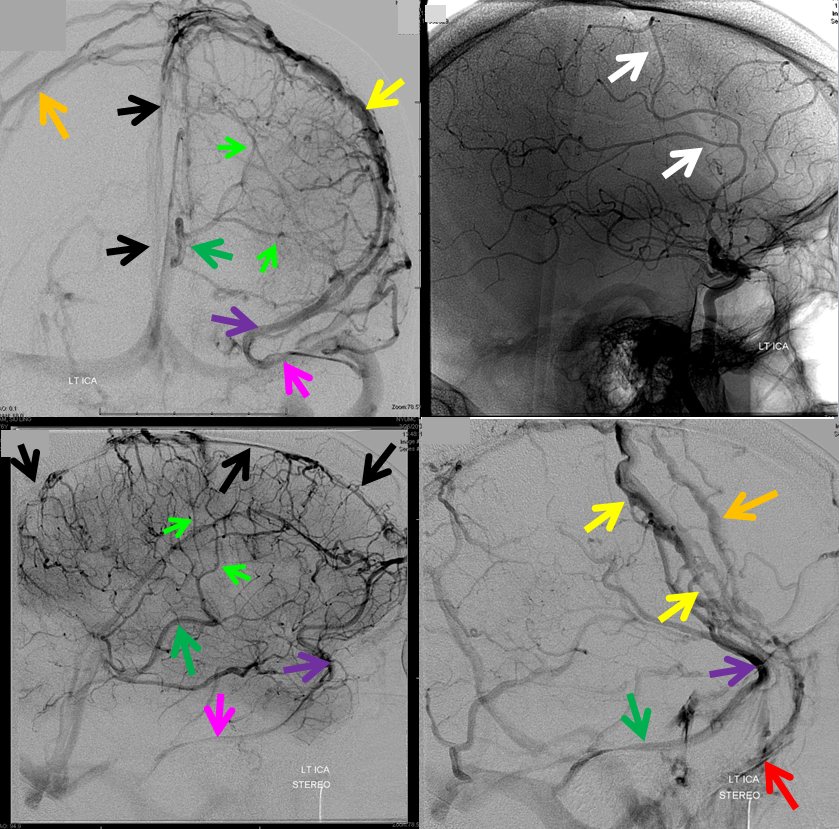

The general neurosurgical fact that the anterior third of the superior sagittal sinus can be safely sacrificed is true almost all the time. When it is not, consequences can be catastrophic. Normally, few veins drain into the anterior 3rd of the SSS, and these usually have collaterals. However, occasionally a large frontal or sylvian vein happens to drain anteriorly. Taking this sinus means risking a venous infarct. Here is an extreme example of dominant inferior left frontal vein draining into the anterior third of the frontal sinus, on MRI. Case courtesy Dr. Howard Riina

Angio is much easier to appreciate. It is well to learn how to spot these veins on MR or CT, as most patients don’t get presurgical angiography for nonvascular lesion

Anaglyph stereo

Below is a case of severe venous sinus thrombosis and secondary parenchymal venous infarcts

The explanation for the above tragic pattern is below. On the right, sigmoid and transverse sinuses are patent. However, the Labbe is hypoplastic, and majority of outflow used to go to the Trolard, into the now occluded SSS. There is no other effective way to go — the trolard tries to decompress via a left diploic vein, and convexity tries to access the deep venous system (which normally should not be well-seen in setting of hypoplastic right A1 segment). The left situation is much better, as well-developed superficial sylvian veins drain into the patent Cavernous Sinus. Thus, despite thrombosis of the left transverse and sigmoid sinuses, the left hemisphere is doing better, while the right one, which has patent transverse and sigmoid sinuses, is devastated.

Post venous thrombectomy — with limited results. Note presence of same left diploic vein as seen in right ICA injection, and connection between the distal superior sagittal sinus and the deep venous system via the inferior sagittal sinus.

Sagittal Sinus Thrombosis — collaterals.

All of the above anatomic knowledge can become very useful in evaluation of venous thrombosis. Numerous collateral pathways develop in this setting attempting to compensate for the loss. The most dramatic cases usually involve the largest channel — the superior sagittal sinus. In this case, a man presented with what initially was thought to be vasculitis-related brain hemorrhage. Subsequent workup led to an angiogram, where sagittal sinus thrombosis with extensive trans-cerebral and trans-osseous emissary vein collateral channels was seen. In retrospect, these findings were present on the patient’s earlier contrast MRI. “Venovibe” or other contrast-enhanced MR venograms can very sensitive, particularly when interpreted with the appropriate index of suspicion. Noncontrast 2-D time of flight MRV I consider to be next to useless as a problem-solving technique. Any thin-slice postcontrast T1 study is vastly superior.